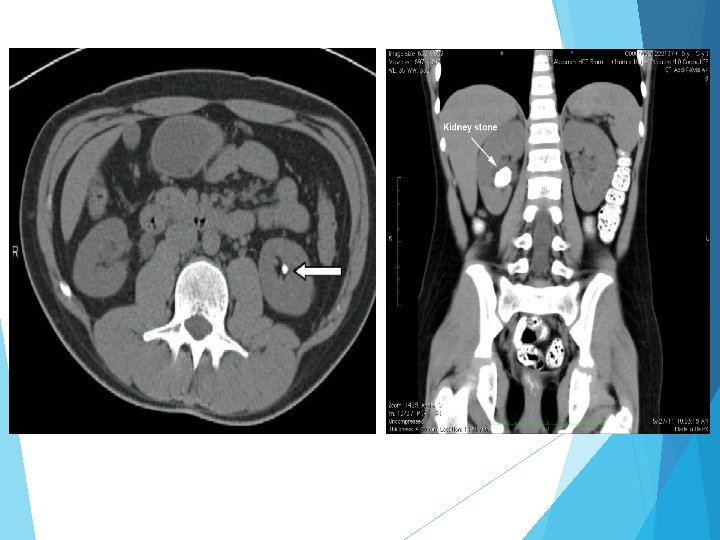

Direkt üriner sistem grafisi (DÜSG) Ultrasonografi İntravenöz pyelografi (IVP) Nükleer radyoloji Bilgisayarlı tomografi (Non kontrast Spiral BT)

BT BT’de hastalar daha az radyasyona maruz kalır ve kontrast ajan kullanılmaması avantajını sağlar. Bt’nin başka bir avantajı da ürik asit ve ksantin taşları gibi non-opak taşları da görüntüleyebilmesidir. Akut yan ağrısı olan hastalarda kontrastsız abdomen tomografi (NCCT), zaman içinde IVP’nin yerini almış ve standart yaklaşım haline gelmiştir NCCT, IVP ile karşılaştırıldığında daha yüksek sensitivite ve spesifite göstermektedir )%95 -97). BMI <30 olan hastalarda NCCT çekilecekse düşük doz NCCT çekilmesi önerilmektedir.